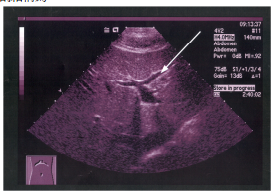

70 附圖中箭號所指的部分為:

(A)門靜脈 (B)肝動脈 (C)左肝靜脈 (D)中肝靜脈